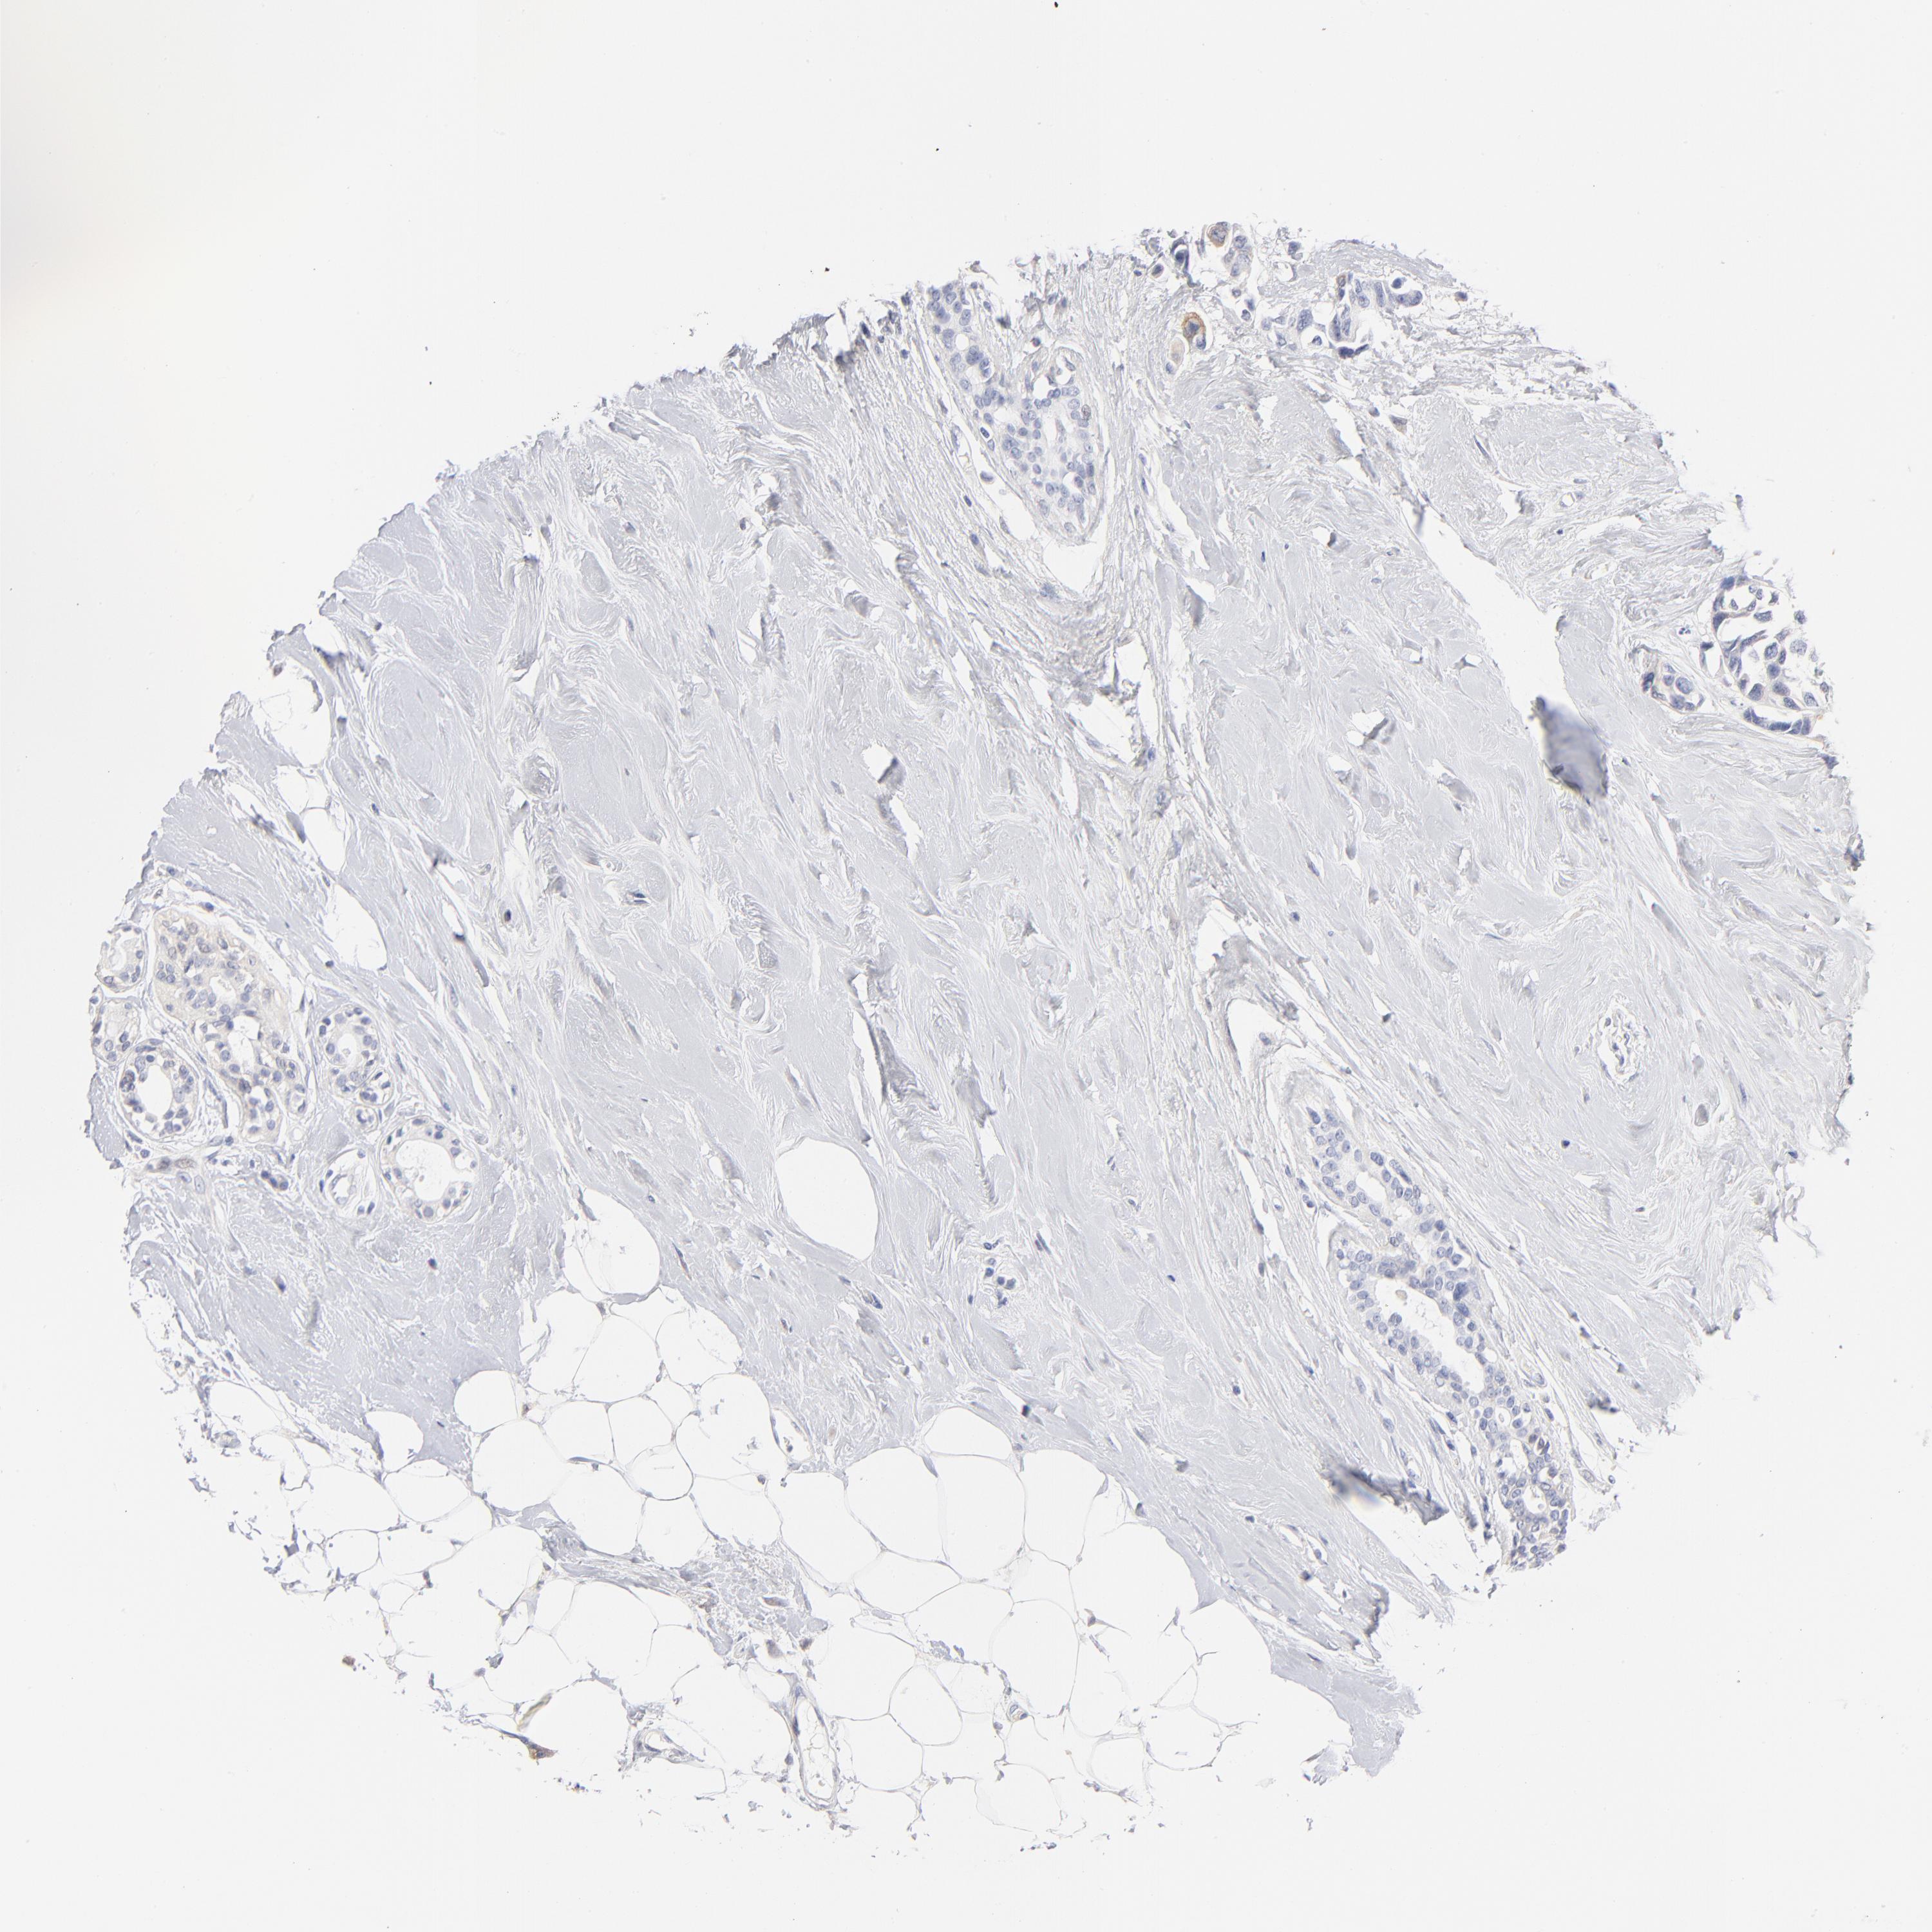

CANCER BREAST CANCER Show tissue menu

BRCA TCGA BRCA VALIDATION PROTEIN EXPRESSION

ANTIBODIES

AND

VALIDATION